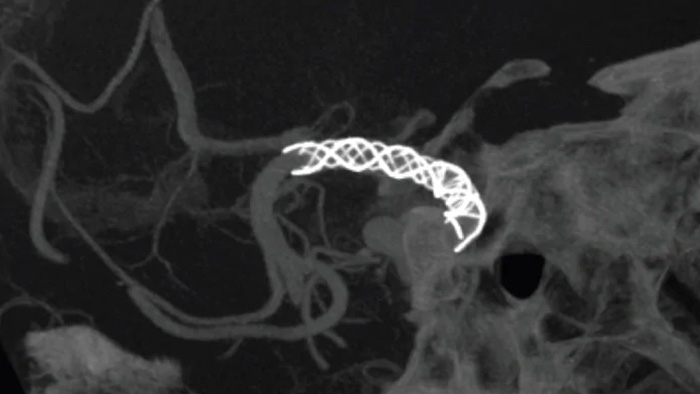

Améliorez la visualisation des stents endovasculaires, des flow diverters et d’autres dispositifs, ainsi que la morphologie des vaisseaux jusqu’à la veine perforante avec SmartCT Vaso. Cette technique d’acquisition est basée sur une acquisition Cone Beam CT et une injection de produit de contraste intra-artérielle. Elle est de plus en plus utilisée pour le suivi des anévrismes traités avec des stents de flow diverter afin de vérifier le positionnement du dispositif.

SmartCT Angio fournit une vue volumétrique en quelques secondes pour faciliter l’évaluation de l’emplacement, de la taille, du cou et de la gravité de l’anévrisme pour la planification du traitement. Les volumes 3D sont visualisés avec une résolution spatiale élevée et une compensation automatique des mouvements du patient.